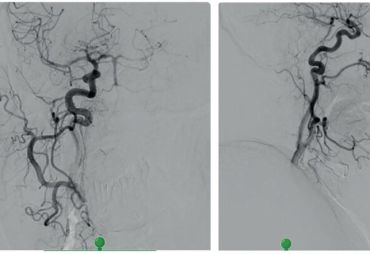

Na zobrazení MR DW (MR obraz s difuzním vážením) byly patrné čerstvé ischemické změny v dolní části levé mozečkové hemisféry v teritoriu PICA (arteria cerebelli inferior posterior) vlevo, a dále v bazi levého brachium pontis. Drobné změny jsou i v teritoriu horní mozečkové tepny vlevo a drobný okrsek restrikce MR DW v dolním okraji pravé mozečkové hemisféry v teritoriu PICA vpravo (obr. 1). Na CTA (výpočetní tomografie – angiografie) a DSA (digitální subtrakční angiografie) byl patrný uzávěr odstupu obou vertebrálních arterií (obr. 2). Zadní mozkové řečiště, tzn. bazilární tepna (BA), PCA a distální části vertebrálních tepen, se plnilo retrográdně cestou zadních komunikant (obr. 3). Retrográdní tok v levé a. vertebralis dosahoval až do extrakraniálního úseku V3 v oblasti oblouku prvního krčního obratle C1 (obr. 4). Nová vyšetřovací modalita QMRA prokázala retrográdní tok v levé zadní komunikantě 30 ml/min a sotva detekovatelný retrográdní tok v bazilární arterii 17 ml/min (obr. 5).